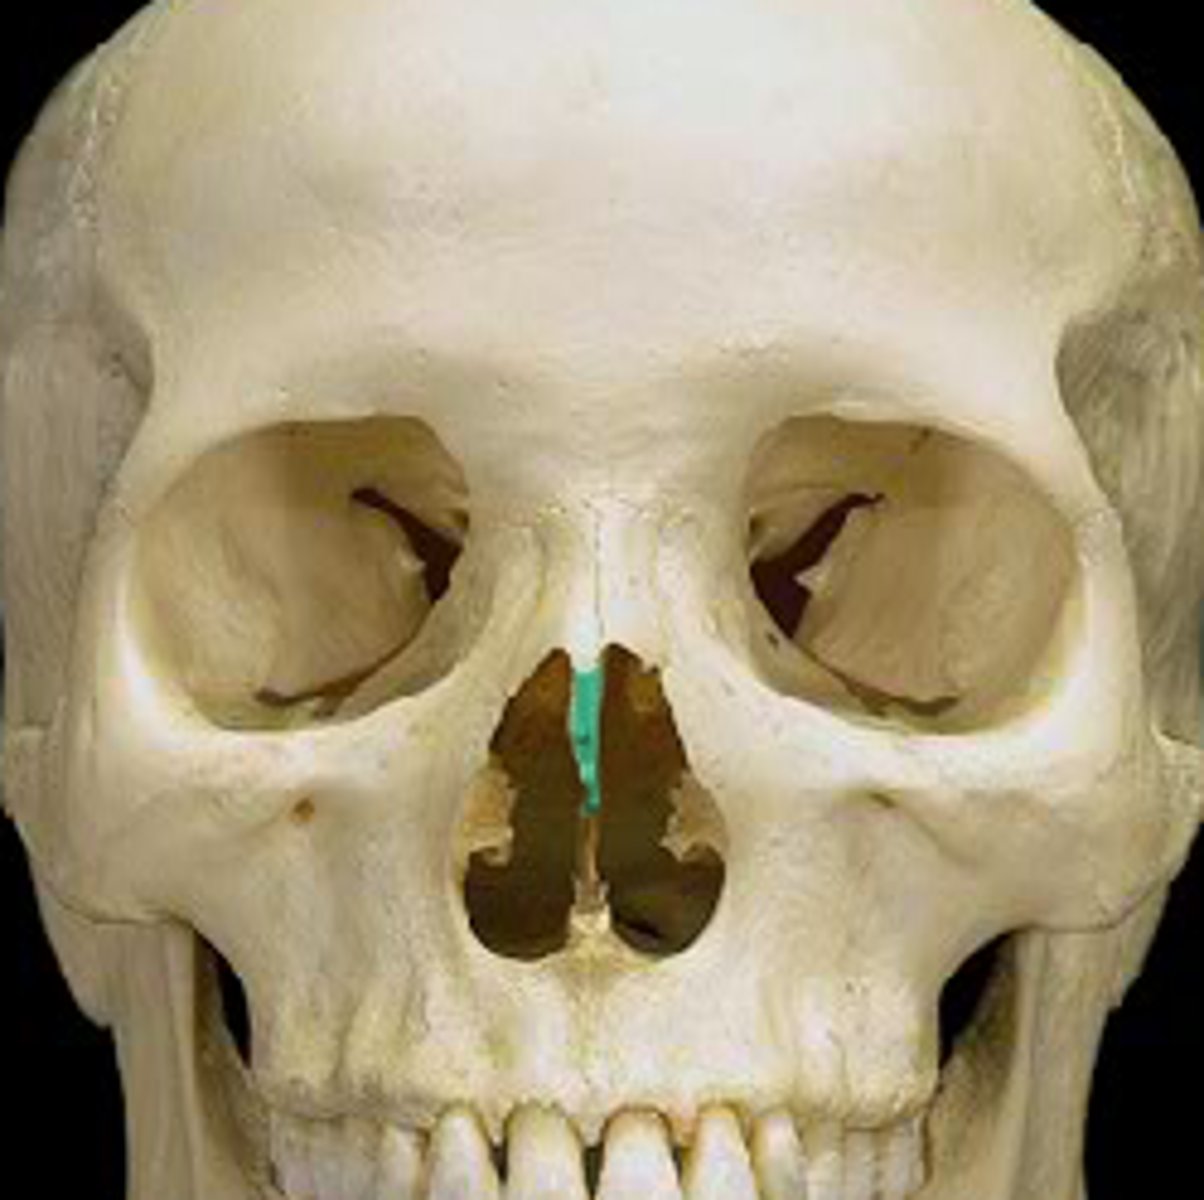

Ethmoid bone

crista galli

perpendicular plate

nasal bones

lacrimal bones

maxillary bones

infraorbital foramen

anterior nasal spine

acanthion

vomer

vomer

lacrimal bone